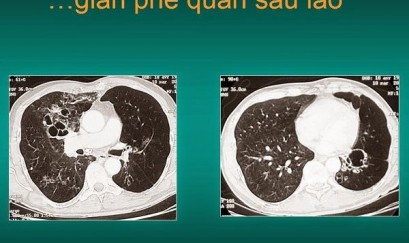

Thông tin cần biết về giãn phế quản sau lao